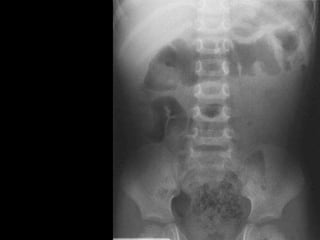

Plain x-ray abdomen

• May be normal.

• Meniscus sign:

• Crescent of gas within colonic lumen that

outlines the apex of intussusceptum.

• Little air in small intestine.

Meniscus

sign

Plain x-ray abdomen • May be normal. • Meniscus sign: • Crescent of gas within colonic lumen that outlines the apex of intussusceptum. • Little air in small intestine.